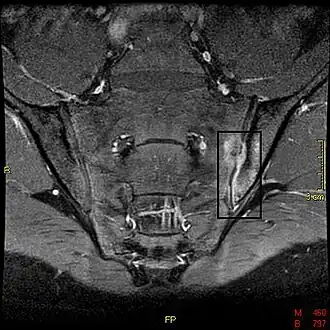

If these criteria still do not give a compelling diagnosis magnetic resonance imaging (MRI) may be useful.[18][20] MRI can show inflammation of the sacroiliac joint.

Options for earlier diagnosis are tomography and MRI of the sacroiliac joints, but the reliability of these tests is still unclear.

T1-weighted MRI with fat suppression after administration of gadolinium contrast showing sacroiliitis in a person with ankylosing spondylitis -